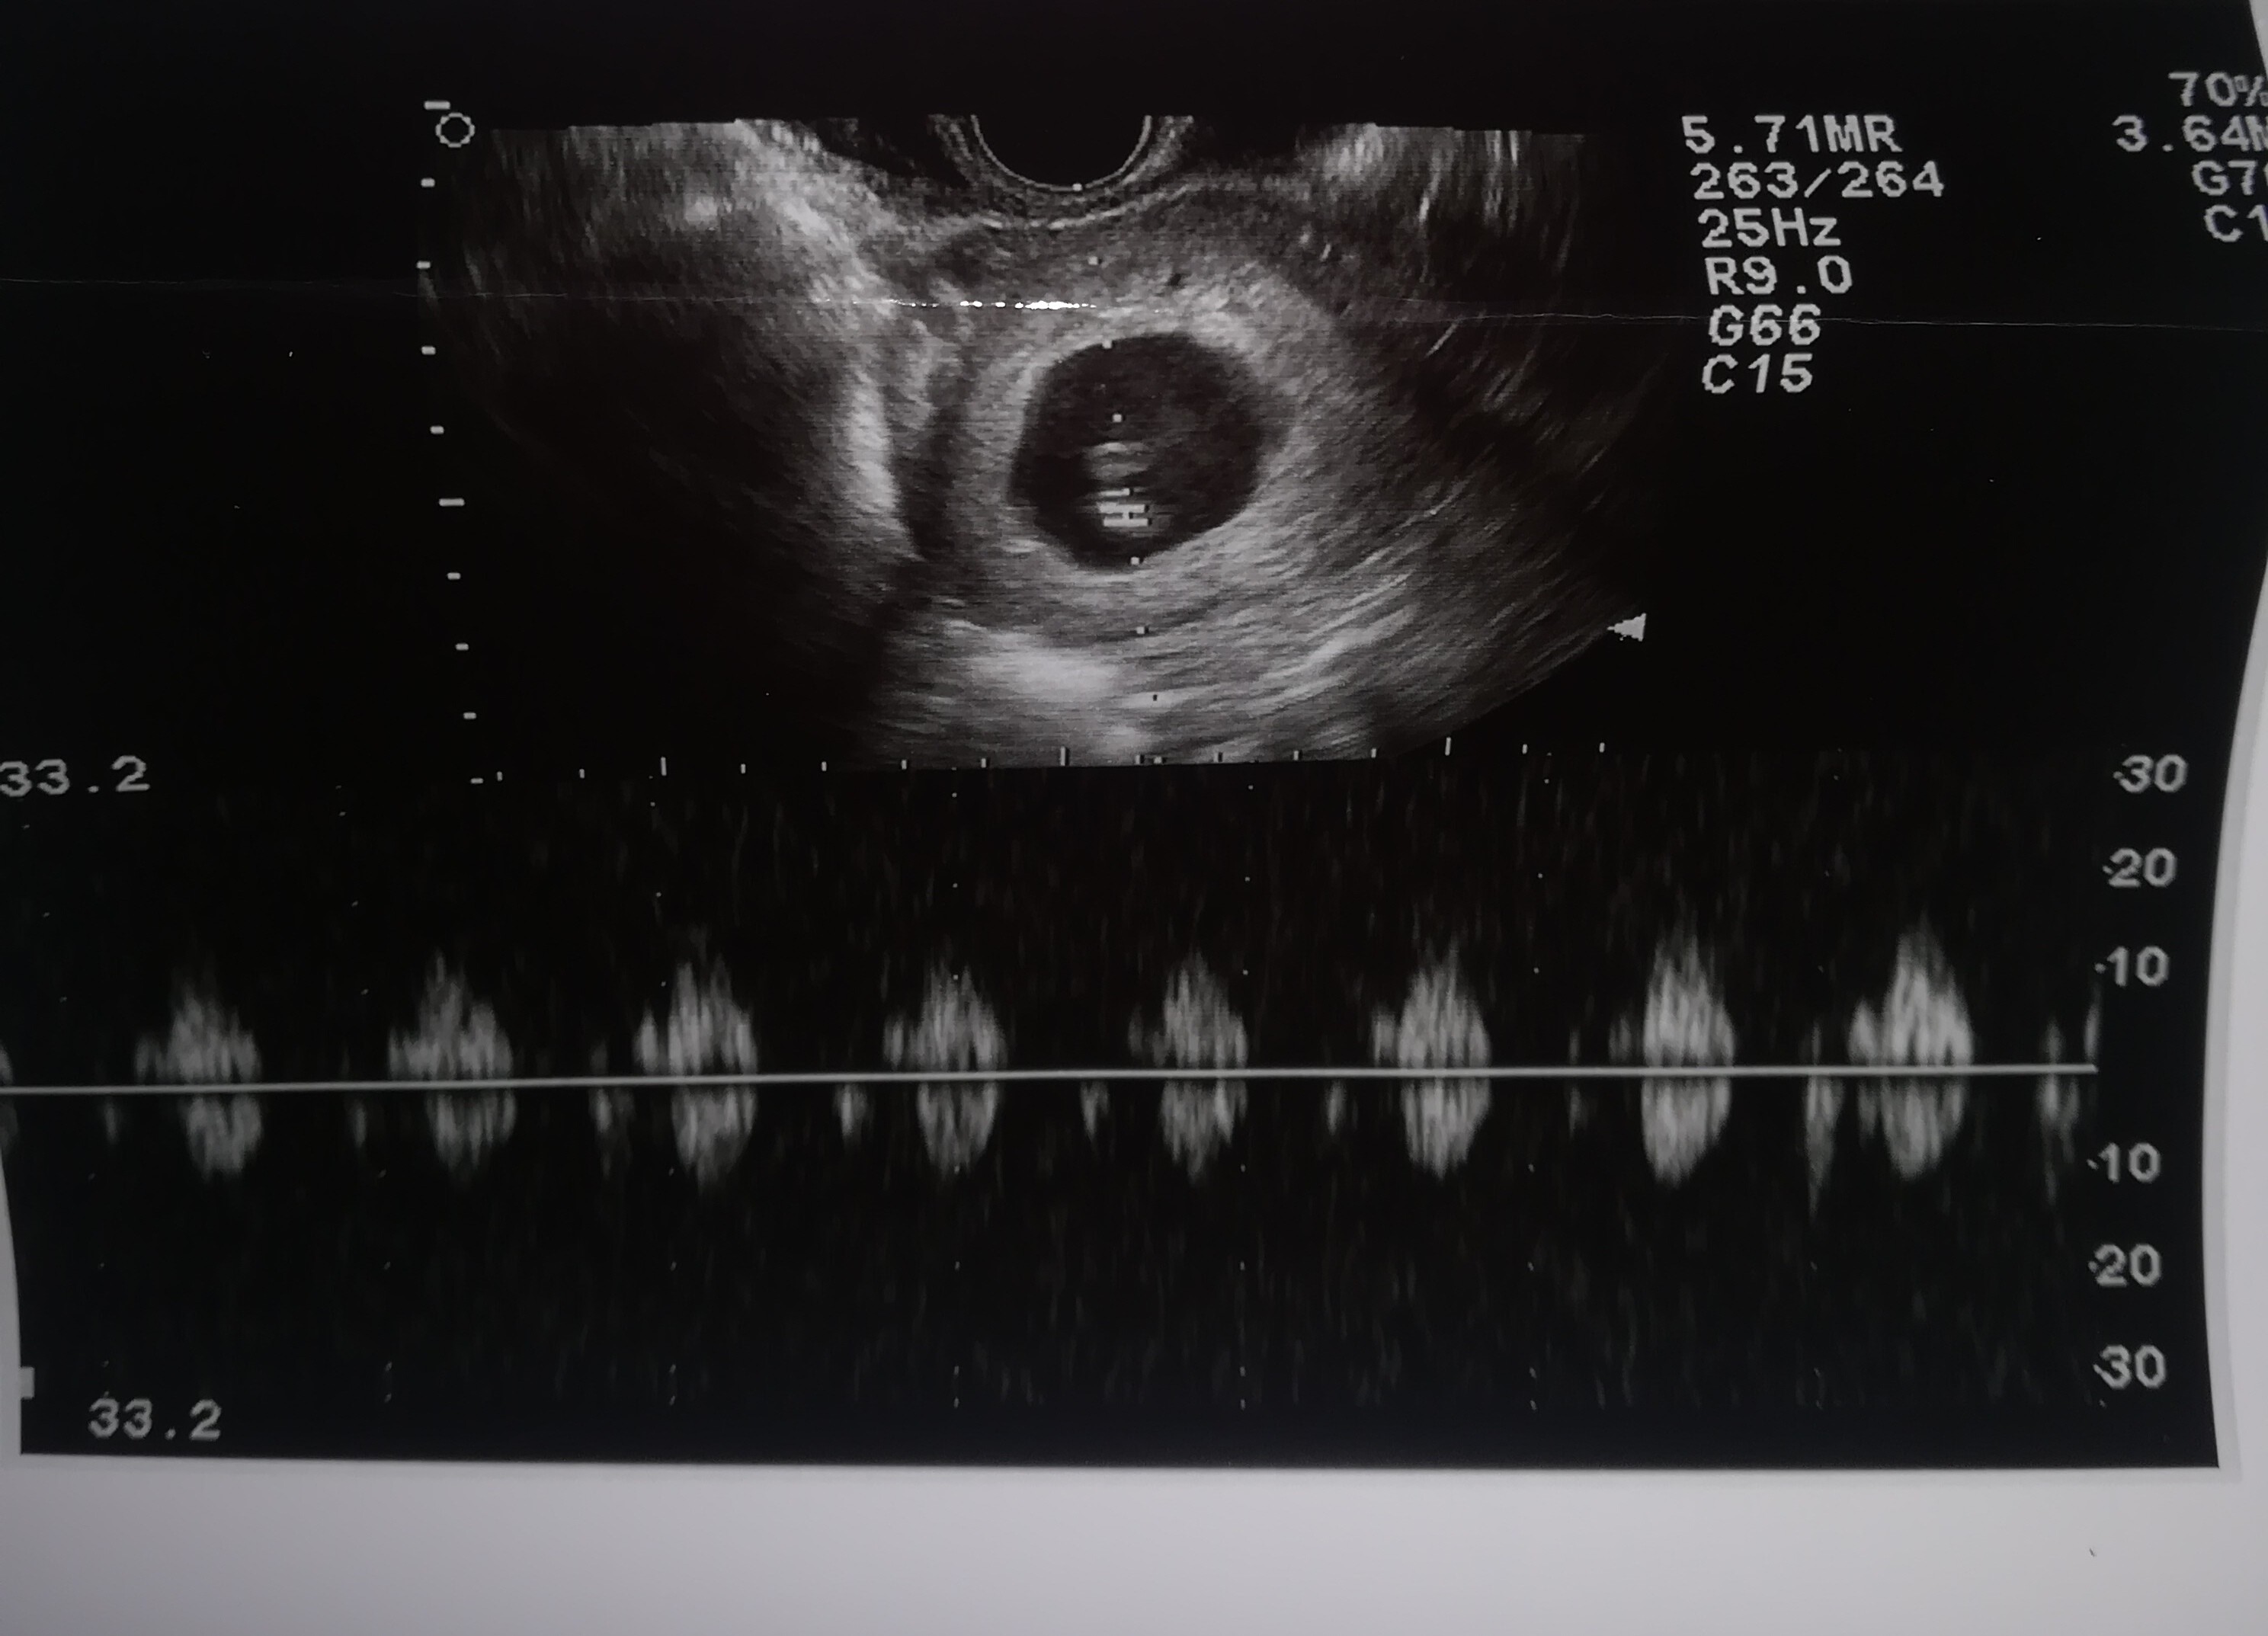

Tak,w piątek pojechałam z plamieniem a na usg stwierdzono brak akcji serca . Dostałam skierowanie do szpitala,i w razie gdyby samo "ruszyło" mam jechać odrazu ale póki co czekam... To chyba jeszcze gorsze to czekanie , chyba wolę to mieć za sobą [emoji25][emoji2731]